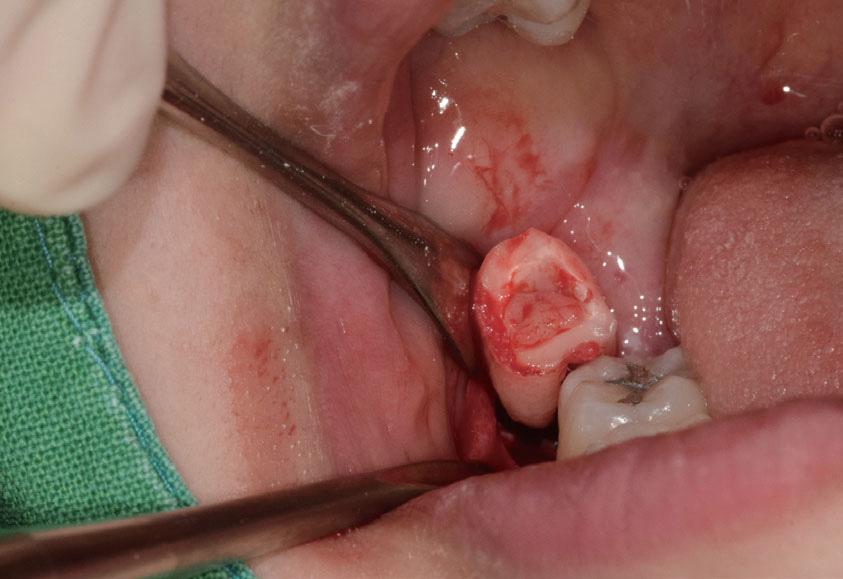

Il seguente caso chirurgico è di un 4.8 mesio-inclinato e parzialmente incluso. Dopo un’incisione a busta, il

dente è stato separato al centro per fare una coronectomia, prima della porzione distale e successivamente della porzione mesiale. Facendo leva quindi è stato possibile rimuovere le radici unite. Figg. 165-172

Figg. 165-172 - Caso 3: tecnica di estrazione con divisione orizzontale utilizzando il manipolo dritto. Fig. 165 Fig. 166 Fig. 167 Fig. 168 Fig. 169 Fig. 170 Fig. 171 Fig. 172